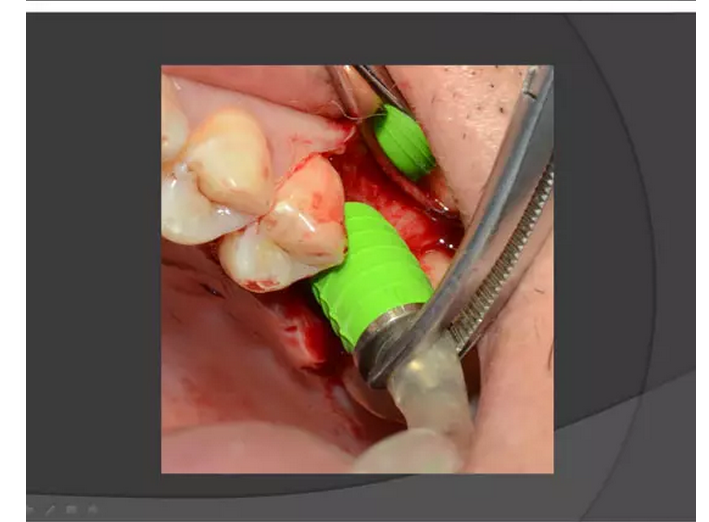

上頜竇種植手術(shù)概述

王漢禹